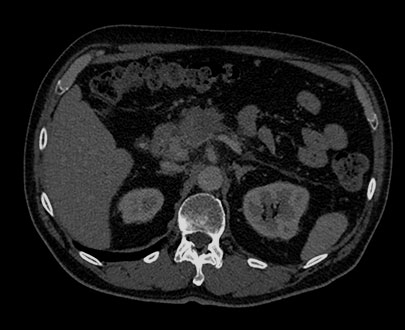

Click the energy level from 40 keV to 200 keV to view structures according to their spectral attenuation properties.

The MonoE view shows synthesized monoenergetic images at predefined keV values from 40 to 200. The appearance of the images changes as the keV values change, even when the window/level settings are unchanged. For example, at lower keV, iodine may appear brighter, and at higher keV, metal artifacts may be reduced.